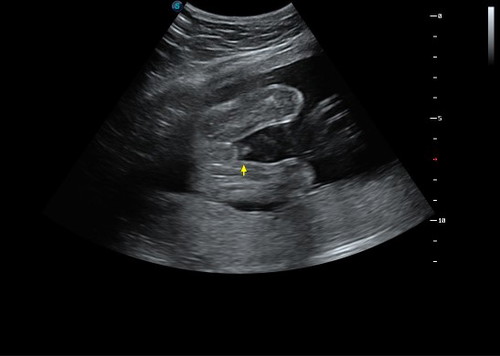

ลูกบ่าวแม่?

หมอบอกไม่ฟันธงหรอก ชายหรือหญิง แต่ที่ชัวร์ๆคือชาย90กว่า% 555555 แม่ๆว่าไงคะ ปล.คุณพ่ออยากได้ลูกสาว #เพื่อความบันเทิงนะคะ ไม่เอาดราม่าคะ^^

น่าจะชายค่ะ แต่ระวังเป็นสายสะดือนะคะ คุณหมอบอกว่าบางคนดูผิดค่ะ

อาจจะผญก็ได้คะ ที่โผล่ออกมาอาจเป็นมือ ทำใจกลางๆไว้คะ

น่าจะชายค่ะเพราบ้านนี้ก็จับได้ท่านี้เหมือนกัน